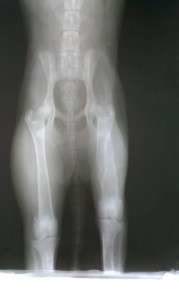

She was wondering on the streets looking for a human with a soul to love her and in return she’ll offer all her love and loyalty. In this way she found a bastard homeless who beaten her till broken her jaw, she has legs problems and who knows what we’ll still discover during investigations but she, kind and loyal soul, was standing and enduring all this treatment without leaving his side unless she was going to look for food when she was hungry. In this way it was succeeded to capture her and now she’s safe, at the clinic, where she’ll receive all the necessary care till she’ll be well in order to take her in our sanctuary from where she’ll leave only to a family that will truly love her.

We have to let Sanny recover from her jaw operation to address the other health issues she faces such as her legs, etc.